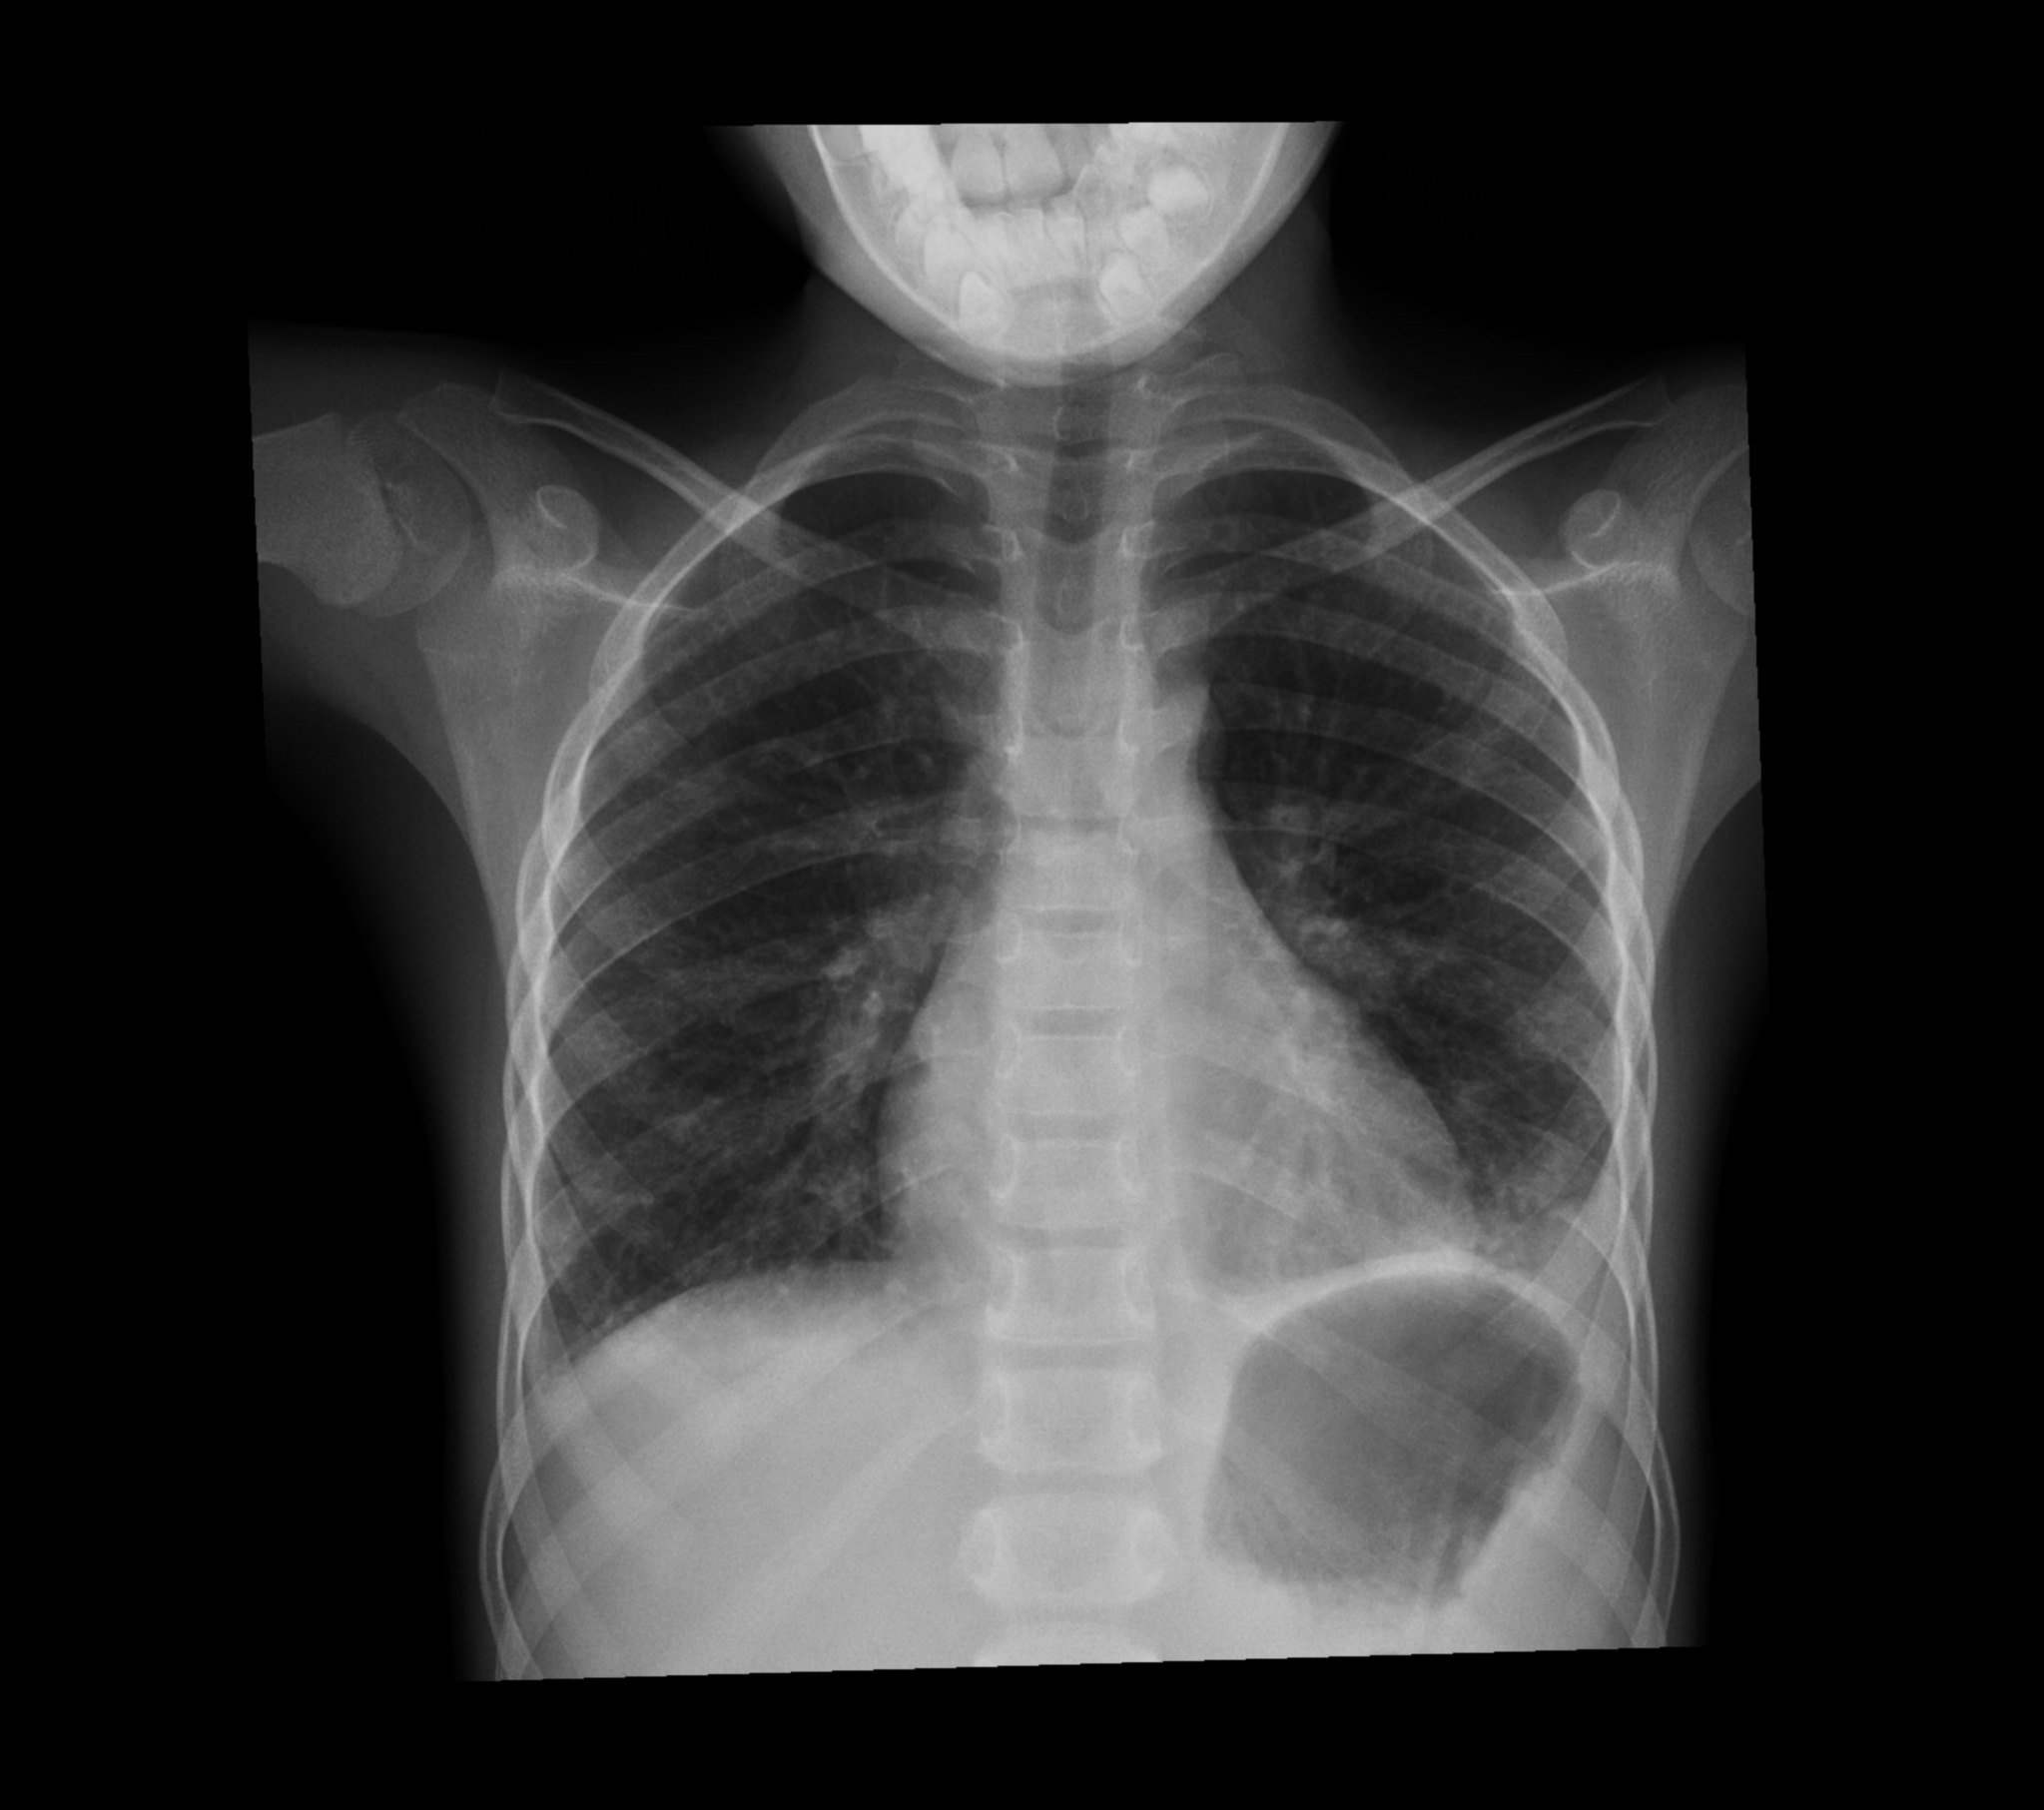

El paciente ha regresado de rayos ¿Qué puede ver en la radiografía?